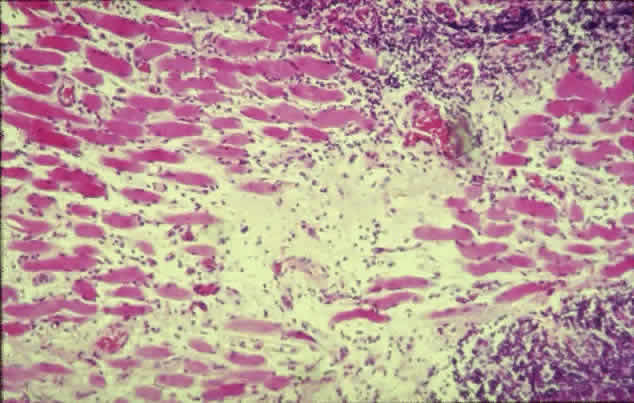

The inflammatory infiltration of the extraocular muscles consists principally of activated T-cells together with smaller numbers of B-cells, macrophages, and mast cells.16 The infiltration is mainly interstitial and is accompanied by increased fibroblastic activity induced by cytokines derived from the immune cells, leading to deposition of glycosaminoglycans and collagen as well as edema. The eventual outcome is fat cell infiltration and fibrosis (Fig. 3). The muscle fibers appear normal, with the exception of subsarcolemmal deposits of lipid and glycogen, and there is an absence of muscle-cell destruction.